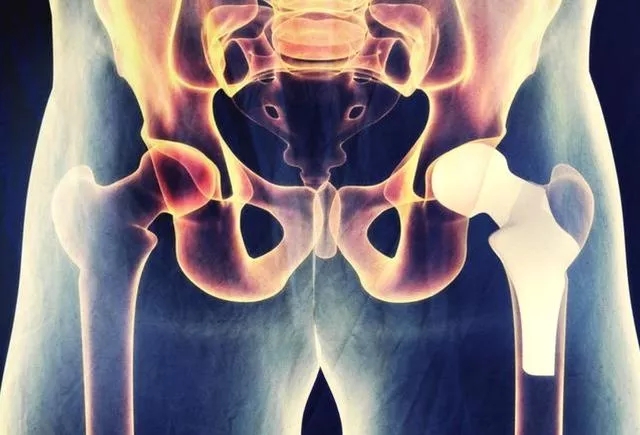

股骨头坏死

股骨头坏死又称股骨头无菌性坏死,或股骨头缺血性坏死,是骨坏死的一种。股骨头局部血运不良,引发股骨头血液循环障碍,从而使得股骨头进一步缺血、坏死、骨小梁断裂、股骨头塌陷的一种病变。因其病因多样、发病隐匿、治疗周期长、致残率高的特点,又被称为“不死的癌症”。

股骨头坏死的诊断

股骨头坏死的治疗效果与病情轻重、发现早晚、病程分期有很大关系,病变发现越早,病情越轻,治疗效果就越好,因此股骨头坏死应做到早期诊断和早期治疗。髋 关节核磁共振、髋关节CT以及同位素骨显像等影像学检查虽然价格较X线片贵,但是往往可以帮助医师更早地发现股骨头坏死。